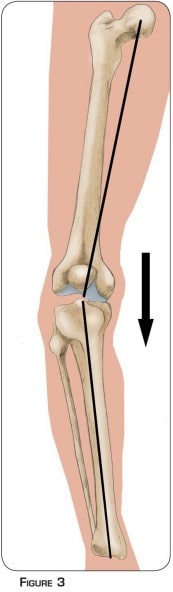

L’arthrose débutante interne est l’usure du cartilage présente entre la partie interne du fémur et du tibia (figure n°2 et photo n°1). La morphologie du membre inférieur en est souvent la cause principale. Sur une forme incurvée, tout le poids du corps passe plutôt par la partie interne du genou (figure n°3). Cette surcharge aboutit à l’usure prématurée du cartilage et du ménisque.